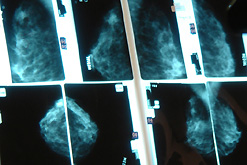

New breast cancer drug |

It has been announced at the Fourth European Breast Cancer Conference that Faslodex, the first of a new kinder class of breast cancer drug, is to be launched in Britain this summer.